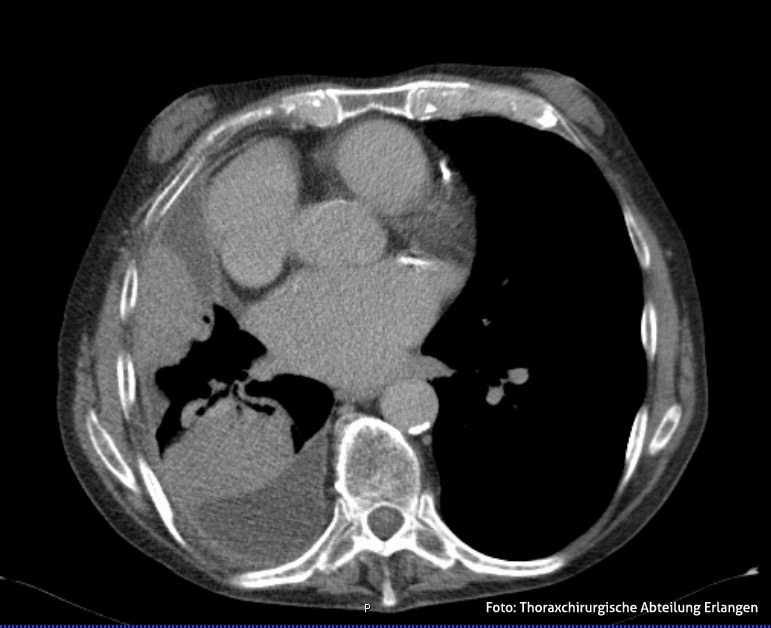

Besteht der Verdacht auf ein Pleuraempyem, so erfolgt zunächst eine körperliche Untersuchung, bei der der Arzt die Brustkorboberfläche abklopft und den Brustkorb sowie die Atemwege abhört. Hinweise auf ein Pleuraempyem wären ein gedämpfter Klopfschall und verminderte Atemgeräusche. Die Festigung der Diagnose erfolgt anschließend durch eine Röntgen- bzw. CT-Aufnahme, wobei eine CT-Untersuchung zur präoperativen Lagebestimmung bzw. Ausdehnung der Eiteransammlung unerlässlich ist.